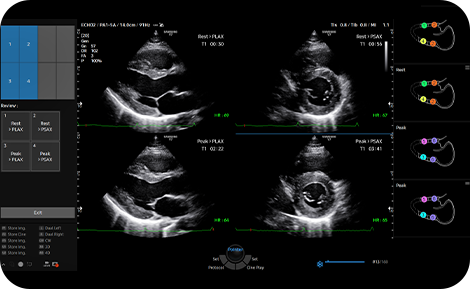

Quantify wall motion of the

left ventricle

Strain+ is a quantitative tool for measuring global and segmental wall motion of the left ventricle (LV). Three standard LV views and a Bull's Eye are displayed in a quad screen for easy and quick assessment of the LV function.

medical diagnostics : Strain+